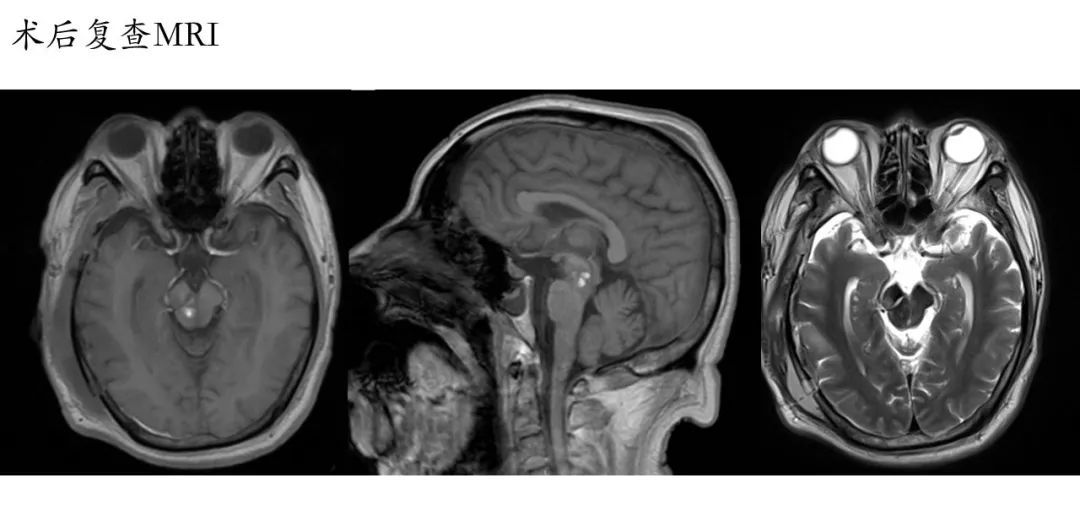

术前影像:透明隔腔明显增宽,双侧脑室、三脑室、脚间池明显扩张、积水,周围脑实质受压,胼胝体受压变薄。弥散加权图像未见异常。中线结构居中。增强扫描未见异常强化。

术前诊断:三脑室内囊肿,幕上脑积水。